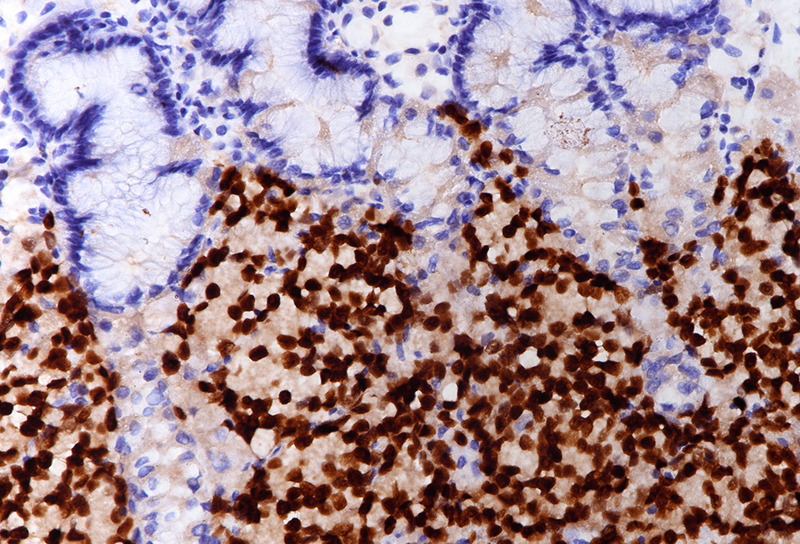

Gastric biopsy in a 67-year-old male with peritoneal carcinomatosis.

Prostate cancer metastasis to the stomach.

On low power, nodular infiltration of the corpus mucosa by middle-size pale to basophilic tumour cells is seen, arranged in solid nest-like arrangement lacking glandular appearance (Panel C-D). The surface epithelium is not involved, there is no background inflammation, atrophy and/or metaplasia. The tumour cells are positive for pan-keratin, keratin 8/18, however negative for keratins 7 and 20. This peculiar keratin profile prompted staining for Prostate-specific membrane antigen (PSMA, Panel E) and NKX3-1 which is an androgen-regulated, prostate-specific homeobox gene (Panel F). Ultimately, diagnosis of prostate cancer metastatic to the stomach was made.